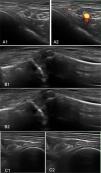

ResultsPatients with RCT had greater mean scores on DAS28-CRP (5.23, 1.28 vs. 3.08, p<0.001), and DAS 28-ESR (5.43, SD=1.28 vs. 3.66, p<0.001). VAS median scores were higher in the RCT group (70.00 vs. 2.00, p<0.001). By ultrasound 12 patients (21%) had acromioclavicular synovitis. Glenohumeral and acromioclavicular arthrosis was found in both groups. No patients had arthritis in the glenohumeral joint.

ResultadosLos pacientes con TMR tuvieron promedios mayores en DAS-PCR (5,23, 1,28 vs. 3,08, p<0,001) y DAS28- VSG (5,43, DE=1,28 vs. 3,66, p<0,001). Las medianas de la escala visual análoga fueron mayores en TMR (70,00 vs. 2,00, p<0,001). Por ultrasonido, 12 pacientes (21%) tenían sinovitis acromioclavicular. En ambos grupos se encontró artrosis glenohumeral y acromioclavicular. Ningún paciente tenía artritis en la articulación glenohumeral.